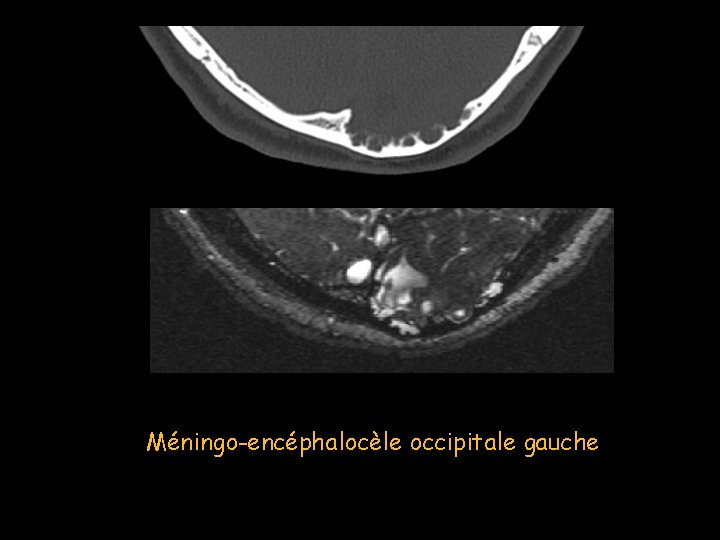

Méningocèle et méningoencéphalocèle • Dysraphie de la ligne médiane. • Occipitale dans 70 % des cas. • Hernie méningée (méningocèle) parfois associée à du parenchyme cérébral (méningoencéphalocèle). • Radiographie standard: Lacune bords nets, type 1 B • L’IRM +++: analyser le contenu exact de ce kyste.

Méningo-encéphalocèle occipitale gauche